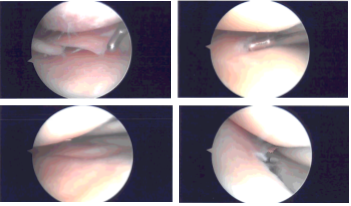

A lateral arthroscopic entry portal was made. The arthroscope was entered. The Medical entry portal was made with the use of a spinal needle. Examination of the medial tibiofemoral compartment showed flap tear of the posterior horn as well as body of the medial meniscus.

Debridement was done with the use of biter as well as shavers. The meniscus was debrided to a balanced margin. There was an interior flap of the margin of the periphery of the body of the meniscus also. This was also removed with the use of shavers.

There was a grade 1 to grade 2 osteochondral lesion of the medial femoral condyle which was debrided with use of shaver and ablator. Examination of the intercondylar notch showed degenerative ACL but intact.

Examination of the lateral tibiofemoral compartment showed intact femoral cartilage. There was fraying and tear of the medial margin of the lateral meniscus which was debrided with the use of shaver and biters.

Examination of the patellofemoral compartment showed grade 1 to grade 2 tear of the lateral facet of the patella which was debrided again with the shaver. There was no osteochondral lesion on the trochlea. The final picture was taken and saved.

Intraoperative Arthroscopy Images